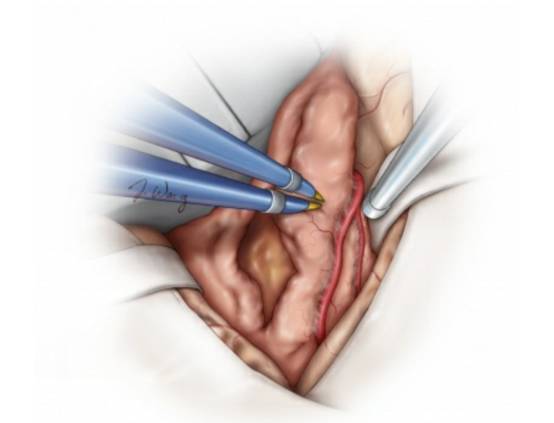

图9. 对实性肿瘤,用超声吸引器(左图)进行去核和分块减压,而对较软的肿瘤组织,用双极电凝、吸引器和垂体咬钳进行减压。接着,笔者会轻轻地牵拉肿瘤包膜,使得其塌陷入已切除的肿瘤核心处(右图)。保持在肿瘤包膜内操作是非常重要的,否则会使得粘附在肿瘤内侧脆弱的脑血管结构受损风险增加。超声吸引器使用时需远离关键血管结构,否则即便没有直接接触,仍可能导致无法修复的血管损伤。